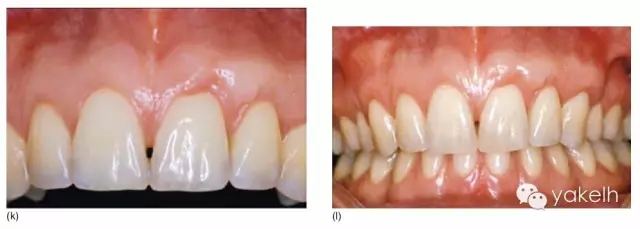

¤¤這類復雜的膜齦手術用于同時處理多個根面Ⅰ類/使Ⅱ類牙齦退縮(圖5.11a~m)。

圖5.11 (a)患者休息放松狀態(tài)下的嘴唇——上下唇不能完全閉合。(b)右上尖牙和側切牙呈Ⅰ類牙齦退縮。(c)左上頜尖牙和側切牙呈Ⅱ類牙齦退縮。(d)先用圓形眼科刀片開始做溝內切口。(e)使用探針在袋內垂直探查貫通隧道,越過膜齦聯(lián)合。(f)使用探針在隧道內橫向探查貫通,保留齦乳頭尖端附著于骨面。(g)從腭部取結締組織移植物,使用絲線牽引,將厚度和大小足夠的結締組織瓣插入隧道內。(h)通過懸吊縫合將組織瓣冠向復位,穩(wěn)定結締組織瓣。(i)術后6個月,上頜右側觀。(j)上頜左側觀,可見牙齦厚度以及色澤的協(xié)調性均得到改善。(k)術后6個月正面觀,牙敏感癥狀消失。(l)術后1年的全口影像,顯示雙側的牙齦退縮均被完全覆蓋,牙齦邊緣增厚且穩(wěn)定,與釉牙骨質界輪廓一致,也與左側中切牙釉質缺損輪廓一致。(m)患者嶄新的笑容,可見側切牙及尖牙的齦緣無退縮。